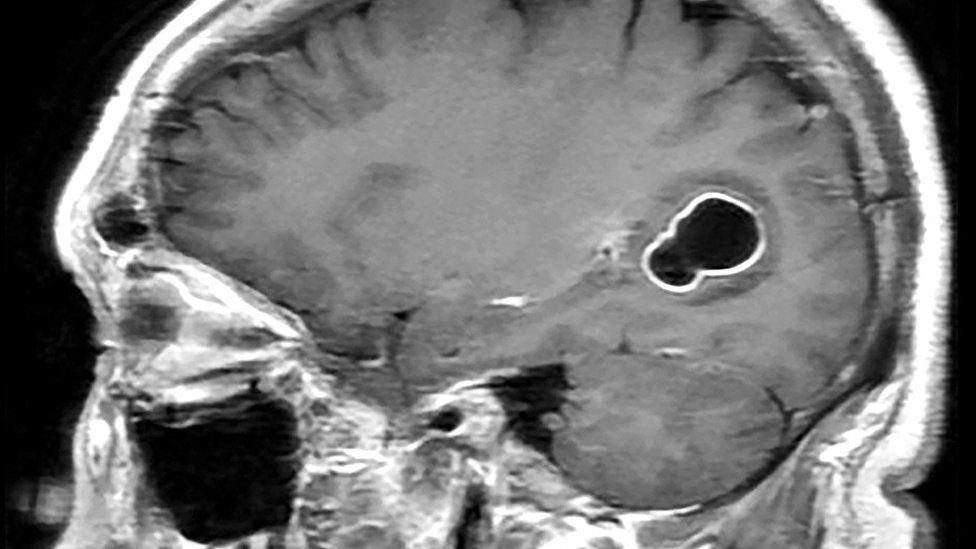

Al realizarle tomografías, los médicos encontraron la presencia de numerosos quistes en el cerebro que, según luego comprobaron con estudios posteriores, en realidad eran larvas de tenia que se habían instalado en su cerebro y que eran las causantes de una infección conocida como neurocisticercosis.

Según los Centros para el Control y la Prevención de Enfermedades (CDC, por sus siglas en inglés) de EE.UU., las larvas de tenia "entran en tejidos como los músculos y el cerebro y forman quistes. Cuando se encuentran quistes en el cerebro, la afección se llama neurocisticercosis".